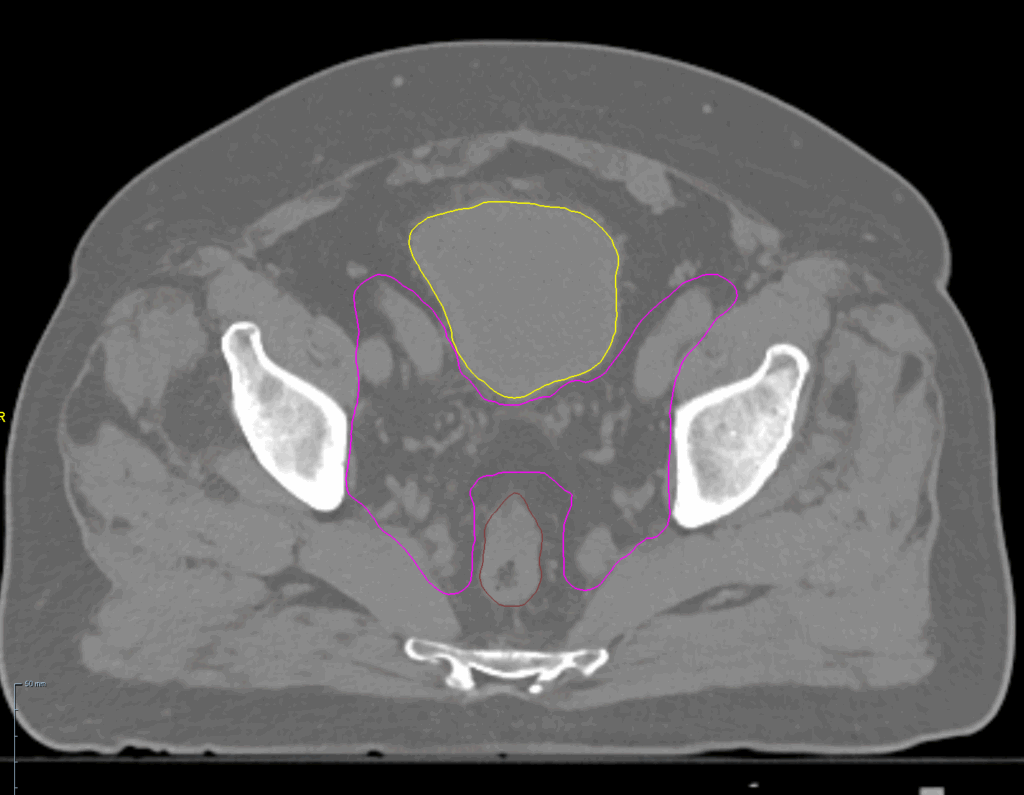

Planning CT Images